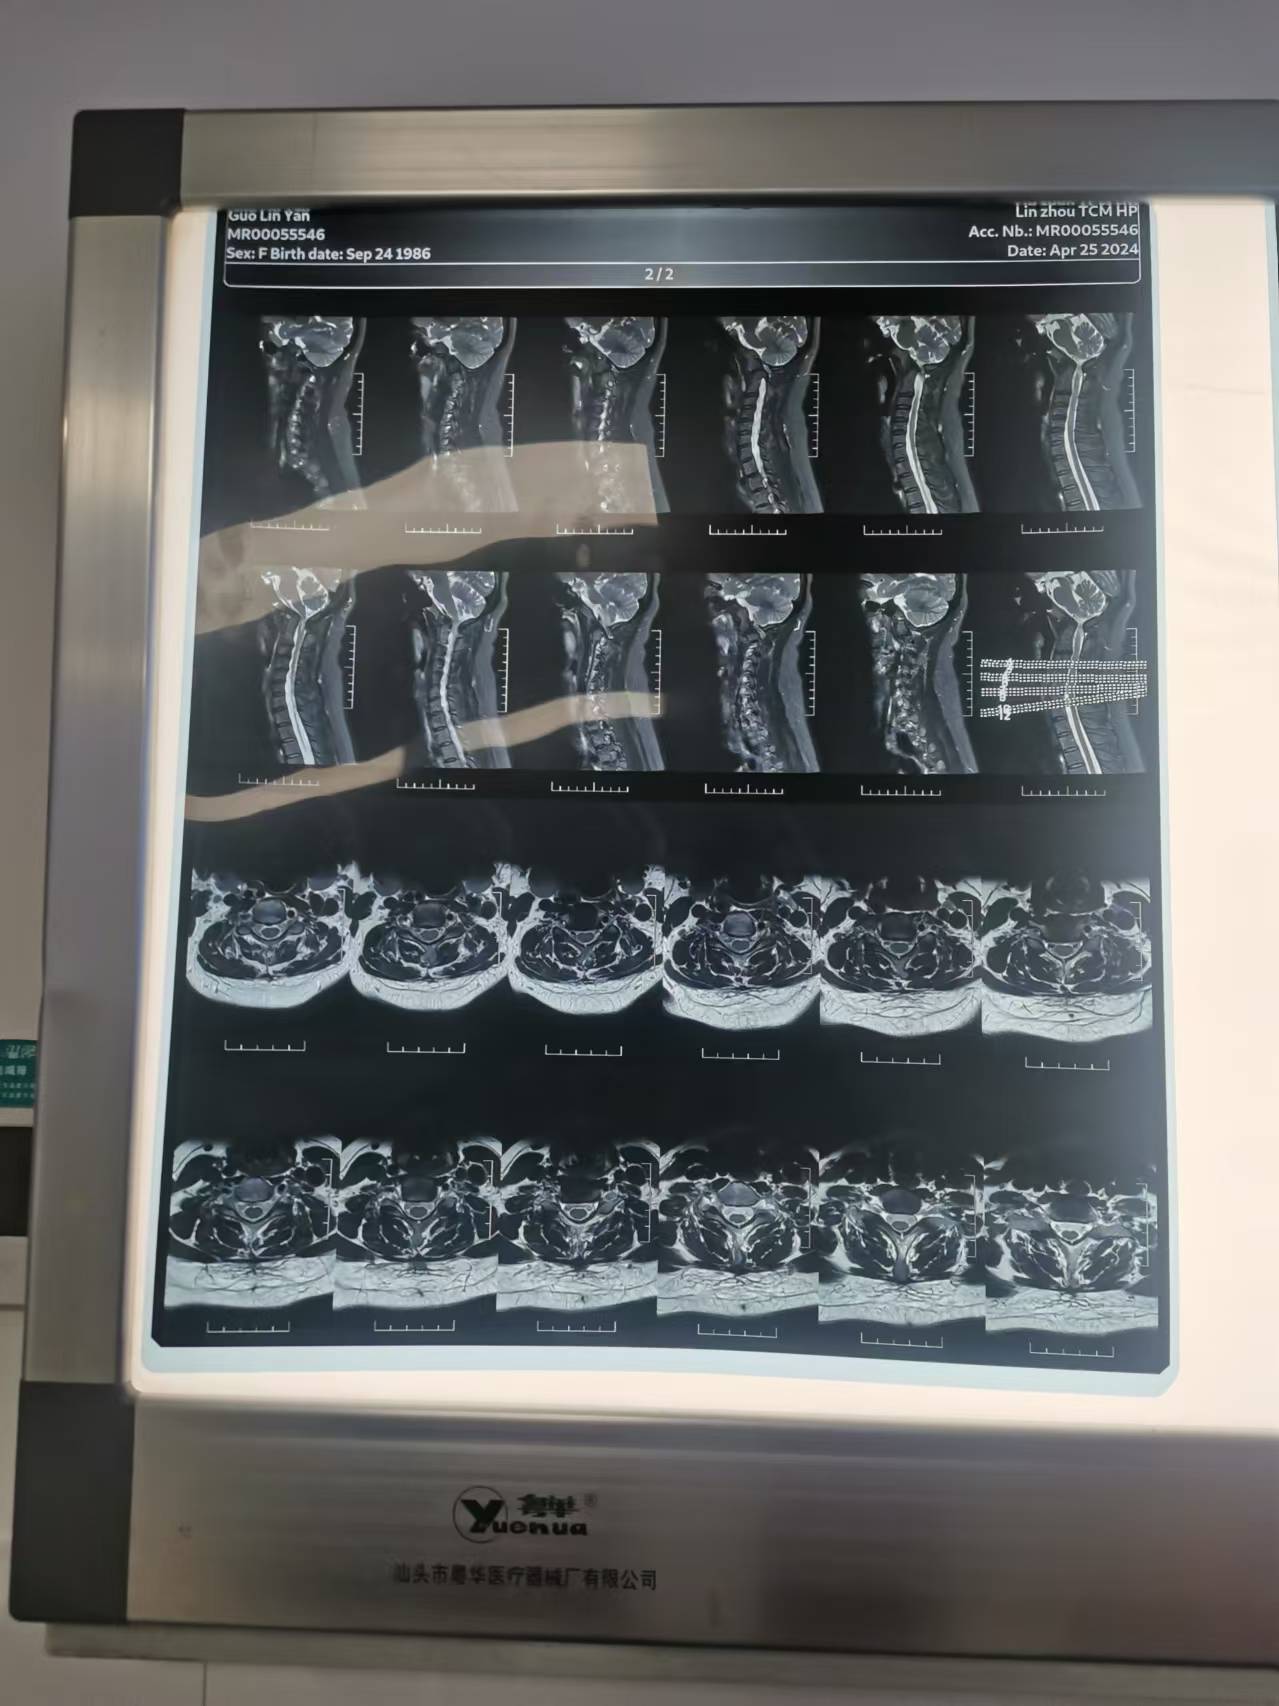

• 诊断日期:2024.04.25

• 诊断:寰枢椎脱位,颅底凹陷

• 影像: